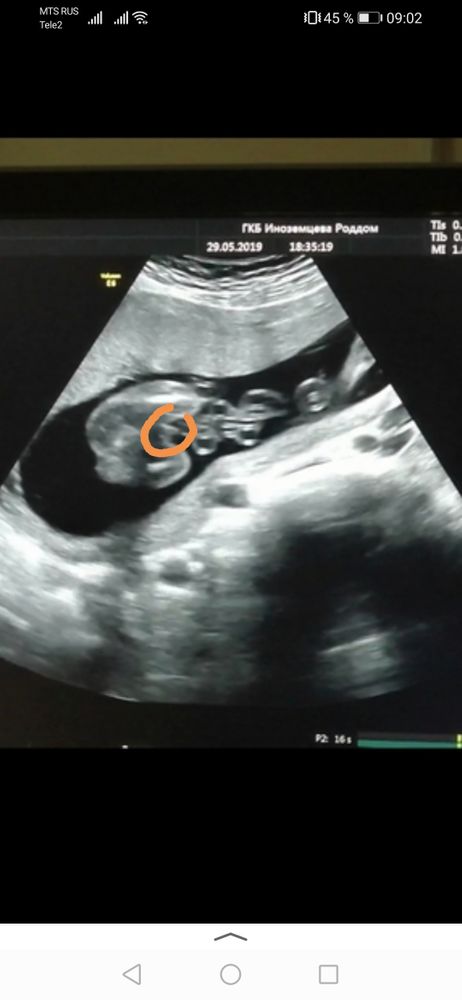

Karmilla, а, вот как это выглядит)) мне на 20ой неделе показали так же из-под низу, что девочка, мол, смотрите, ребёнок не прячется, вот, ничего нет, и я говорю я даже не знаю, как мальчик бы выглядел) теперь знаю 😅